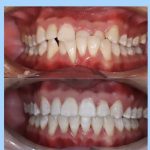

Bir necha yil davomida tish muammolari bilan qiynaldim, lekin bu klinikadagi shifokorlar mening barcha muammolarimni hal qilishdi. Hozir tabassumimni hech narsadan tortinmasdan namoyish etaman. Ular chinakamiga mijozlariga g'amxo'rlik qilishadi. Rahmat!

Men doim stomatologiya muolajalaridan biroz qo'rqardim, lekin bu klinikada hamma narsa o'zgardi! Xodimlar juda samimiy va tajribali. Davolanishning har bir bosqichida o'zimni juda qulay his qildim. Endi tishlarim butunlay sog'lom va go'zal! Bu yerdan xizmat olganimdan juda mamnunman.

Tish muolajalarini bu klinikada olganimdan keyin endi boshqa joy qidirmayman. Shifokorlar ishlarini juda aniq va professional tarzda bajarishdi. Davolanish jarayoni doimiy e’tibor va ehtiyotkorlik bilan amalga oshirildi. Juda minnatdorman!